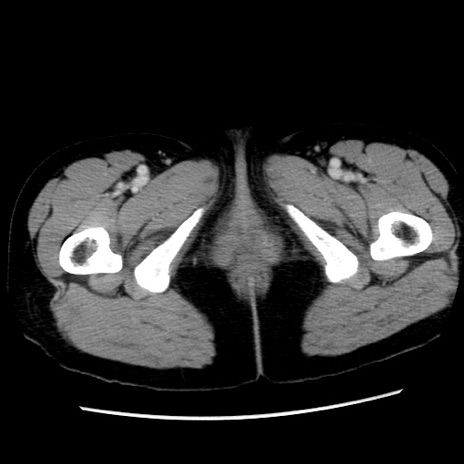

症例10(横断像)

【症例】 50歳代女性

【主訴】 腹痛

【現病歴】前日生レバーを食べた。今朝に排便あり。 昼前に突然発症の腹痛を生じ、当院救急外来を受診した。

【既往歴】 子宮筋腫にてで子宮全摘後

【身体所見】 意識清明、腹部:平坦、軟、下腹部やや左を中心に圧痛・反跳痛あり、筋性防御あり

【データ】WBC 7800、CRP 0.07